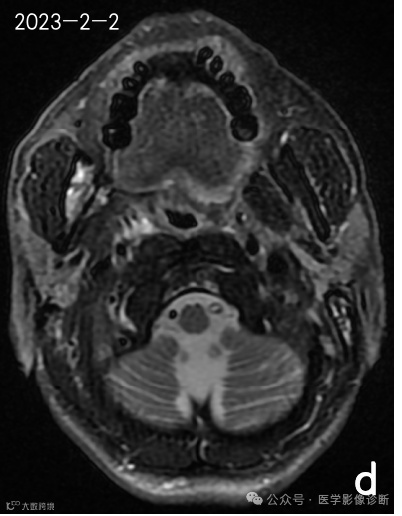

患者,男性,56岁,放疗后患有右口咽癌。

不同时期的四次核磁共振成像显示右下颌骨有异常信号。前两次报告(a、b)均未提及异常信号,说明存在感知错误(漏诊)。在第三次检查(c)中,放射科医生发现了异常信号,但误认为是骨转移,说明存在认知错误(误诊)。患者自2018年以来经常牙龈肿痛的临床查体和治疗情况被遗漏,经过抗炎治疗后,这种症状得到了很大改善。诊断应为右下颌骨骨坏死伴骨髓炎,但放射科医生因不熟悉放疗并发症而导致诊断偏差。